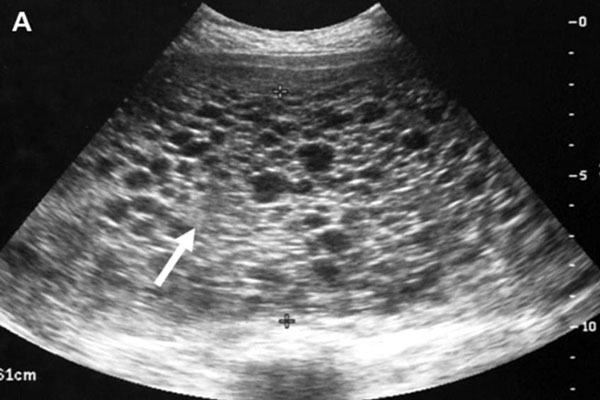

Có thai ngoài tử cung cũng là nguyên nhân siêu âm không thấy thai

Thông thường, trứng sẽ về tử cung của mẹ làm tổ sau khi thụ tinh. Nhưng đôi khi ở những tình huống bất thường, trứng sẽ làm tổ ở một vị trí khác ngoài tử cung. Đây chính là lý do vì sao thử que thấy 2 vạch nhưng siêu âm thì không nhìn thấy thai.

Bác sĩ sẽ tiến hành làm thêm một số xét nghiệm khác để có kết quả chính xác nếu đã có nghi ngờ mang thai ngoài dạ con. Khi đã được chẩn đoán có thai ngoài tử cung, mẹ nên đình chỉ vì có thể dẫn đến nhiều biến chứng rất nguy hiểm cho mẹ như vỡ buồng trứng.